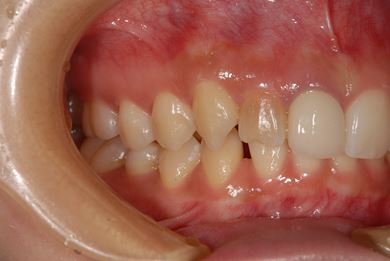

| 性別/年齢 | 女性 / 21歳 | ||||||||||||||||||||||||||||||||

| 主訴 | 歯の変色、欠けた部分を治したい。 | ||||||||||||||||||||||||||||||||

| 治療方針 | 上前歯を根管治療後、オールセラミッククラウンにて審美的回復を行う。 | ||||||||||||||||||||||||||||||||

| 治療内容 | オールセラミッククラウン2本(オールセラミック用土台2本) | ||||||||||||||||||||||||||||||||